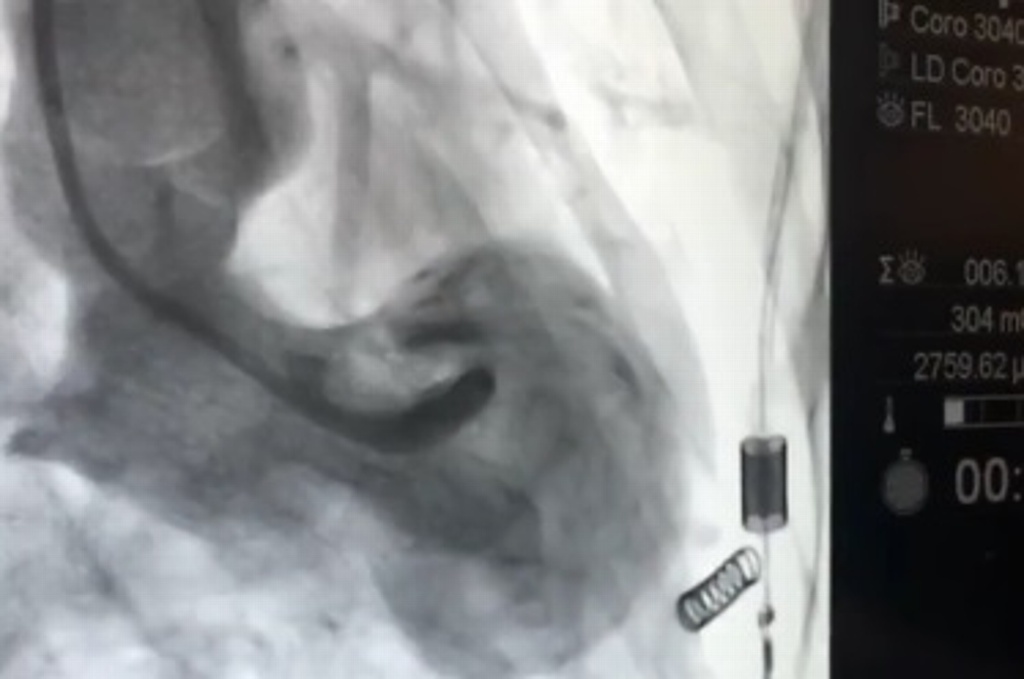

Agregó que en la imagen del “Síndrome del corazón roto” se aprecia la cardiomiopatía de TakoTsubo, que generalmente presenta la forma de un jarrón japonés para sacar pescado, es una afección cardíaca causada por estrés, es un infarto que en realidad no es un infarto, sino la irrupción súbita de hormonas ante la presencia de un estrés o una fuerte impresión.